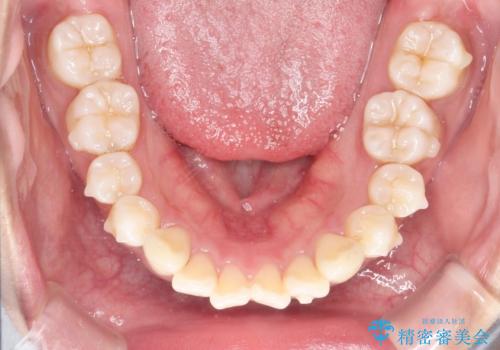

がたがたをインビザラインで整った歯並びへ

- 全体的ながたつきを主訴に来院されました。

抜歯矯正も考えられる状態でしたが、患者様が非抜歯での矯正を希望されたため、歯と歯の間をわずかに削りスペースを作り、全体を整える計画としました。

非常に協力的な患者様でしたので、スムーズに治療を終えることができました。